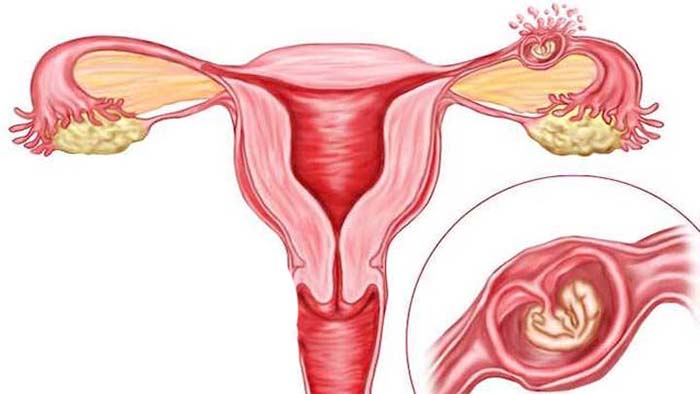

این بیماری زمانی اتفاق میافتد که بافت مشابه با بافت داخلی رحم (آندومتر) در جایی خارج از رحم رشد میکند، معمولاً در تخمدانها، لولههای فالوپ یا سایر اندامهای لگنی. علائم آندومتریوز میتواند شامل دردهای شدید قاعدگی، درد در حین رابطه جنسی، مشکلات باروری و خونریزی غیر طبیعی باشد. با این حال، بسیاری از زنان مبتلا به آندومتریوز ممکن است بدون علائم جدی یا فقط علائم خفیف داشته باشند، که این ممکن است تشخیص بیماری را دشوار کند.

به ندرت، لکه های اندومتریوز در سایر نقاط بدن رخ می دهد. این می تواند باعث ایجاد دردهای غیرعادی در قسمت هایی از بدن شود که همزمان با دردهای پریود رخ می دهد.اندومتریوز باعث می شوددر طول سالیان متمادی تئوری های مختلفی برای علت آندومتریوز وجود داشته است. پوشش داخلی رحم (رحم) آندومتر نامیده می شود. یک نظریه این بود که برخی از سلول های آندومتر به خارج از رحم وارد ناحیه لگن می شوند. وقتی پریود میشوید، با ریختن به سمت عقب در امتداد لولههای فالوپ به آنجا میرسند.لکه های اندومتریوز تمایل دارند "چسبنده" باشند و ممکن است اندام ها را به یکدیگر بپیوندند. اصطلاح پزشکی برای این چسبندگی است. برای مثال، مثانه یا روده ممکن است به رحم «بچسبد». تکه های بزرگ آندومتریوز ممکن است به کیست هایی تبدیل شوند که هر ماه هنگام پریود شدن شما خونریزی می کنند. کیست ها می توانند با خون تیره پر شوند و به عنوان کیست های شکلاتی شناخته می شوند.

آندومتر پوشش داخلی رحم (رحم) است. این بافت به طور معمول در طول چرخه قاعدگی مراحل رشد و ریزش را طی می کند. آندومتریوز زمانی رخ می دهد که آندومتر خارج از محل معمول قرار داشته باشد. اندومتریوز ممکن است در تخمدان ها، لوله های فالوپ، واژن یا سایر قسمت های رحم رخ دهد. به ندرت ممکن است اندومتریوز در شکم و ریه ها رخ دهد.

آندومتریوز با وجود بافت آندومتر در خارج از رحم، یعنی روی تخمدانها، لولههای فالوپ، رباطهای ساکرال رحم (رباطهایی که از رحم حمایت میکنند)، صفاق، مثانه، روده و به ندرت ریهها و حتی مغز مشخص میشود.

اندومتریوز نام خود را از کلمه آندومتر گرفته شده است، پوشش داخلی رحم که بدن شما هر ماه در صورت کاشت تخمک خود آن را تولید می کند. اگر در همان ماه باردار نشوید، آندومتر از بدن شما خارج می شود و به همین دلیل دوره قاعدگی رخ می دهد. گاهی اوقات، این بافت آندومتر از انتهای لوله فالوپ به داخل شکم می رود. در برخی از زنان، بافت به اندام های دیگر متصل می شود. هورمون های ساخته شده در چرخه قاعدگی بعدی این بافت اضافی را تحریک می کند تا رشد کند و بعداً درست مانند بافت رحم ریزش کند. اما این خونریزی و ریزش بافت راهی برای خروج از بدن ندارد که باعث التهاب و تحریک بافت موضعی می شود. معمولاً التهاب باعث دردی می شود که بیماران اغلب با آندومتریوز تجربه می کنند.